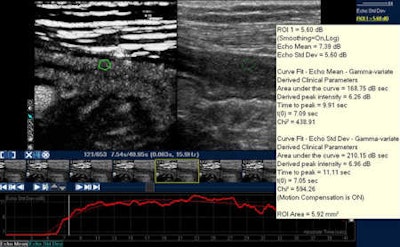

The software makes it feasible to immediately export data in Excel and collect it for future patient visits or comparison with other patients. In a quantification method for CD, it is possible to view the region-of-interest and, during the injection time, the arrival and amount of contrast, as well as the typical wash-in and wash-out curves. Several studies have shown that this technique has both high specificity and sensitivity in evaluating treatment results, but translating these advances into clinical practice remains challenging because one examination is still very different to another.